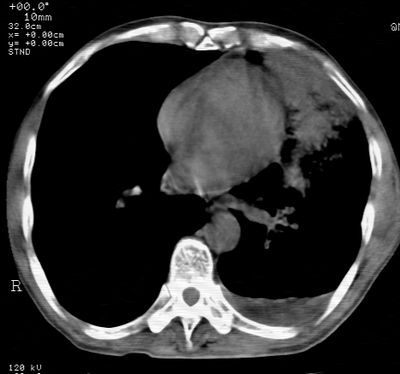

标题: CT24000:M65,胸痛,胸闷月余,既往慢支,肺气肿,肺心病 [打印本页]

标题: CT24000:M65,胸痛,胸闷月余,既往慢支,肺气肿,肺心病

左肺门肿块,相应支气管闭塞,左肺上叶、舌叶大片及散在高密度影,部分呈不张改变,两肺纹粗乱,左侧胸腔积液。考虑左侧中央型肺癌伴阻塞性改变。

左肺门见巨大软组织肿块影,直径约--,境界清,左上肺叶支气管变窄,左上肺舌叶见大片状密实影,余肺纹理增多、紊乱、纤细、部分网格状,两肺透亮度增高,纵隔内见增大多发淋巴结影,心影略左偏,左侧少量胸腔积液。

左侧中央型肺癌伴左上肺舌叶不张、纵隔淋巴结转移,左侧少量胸腔积液。